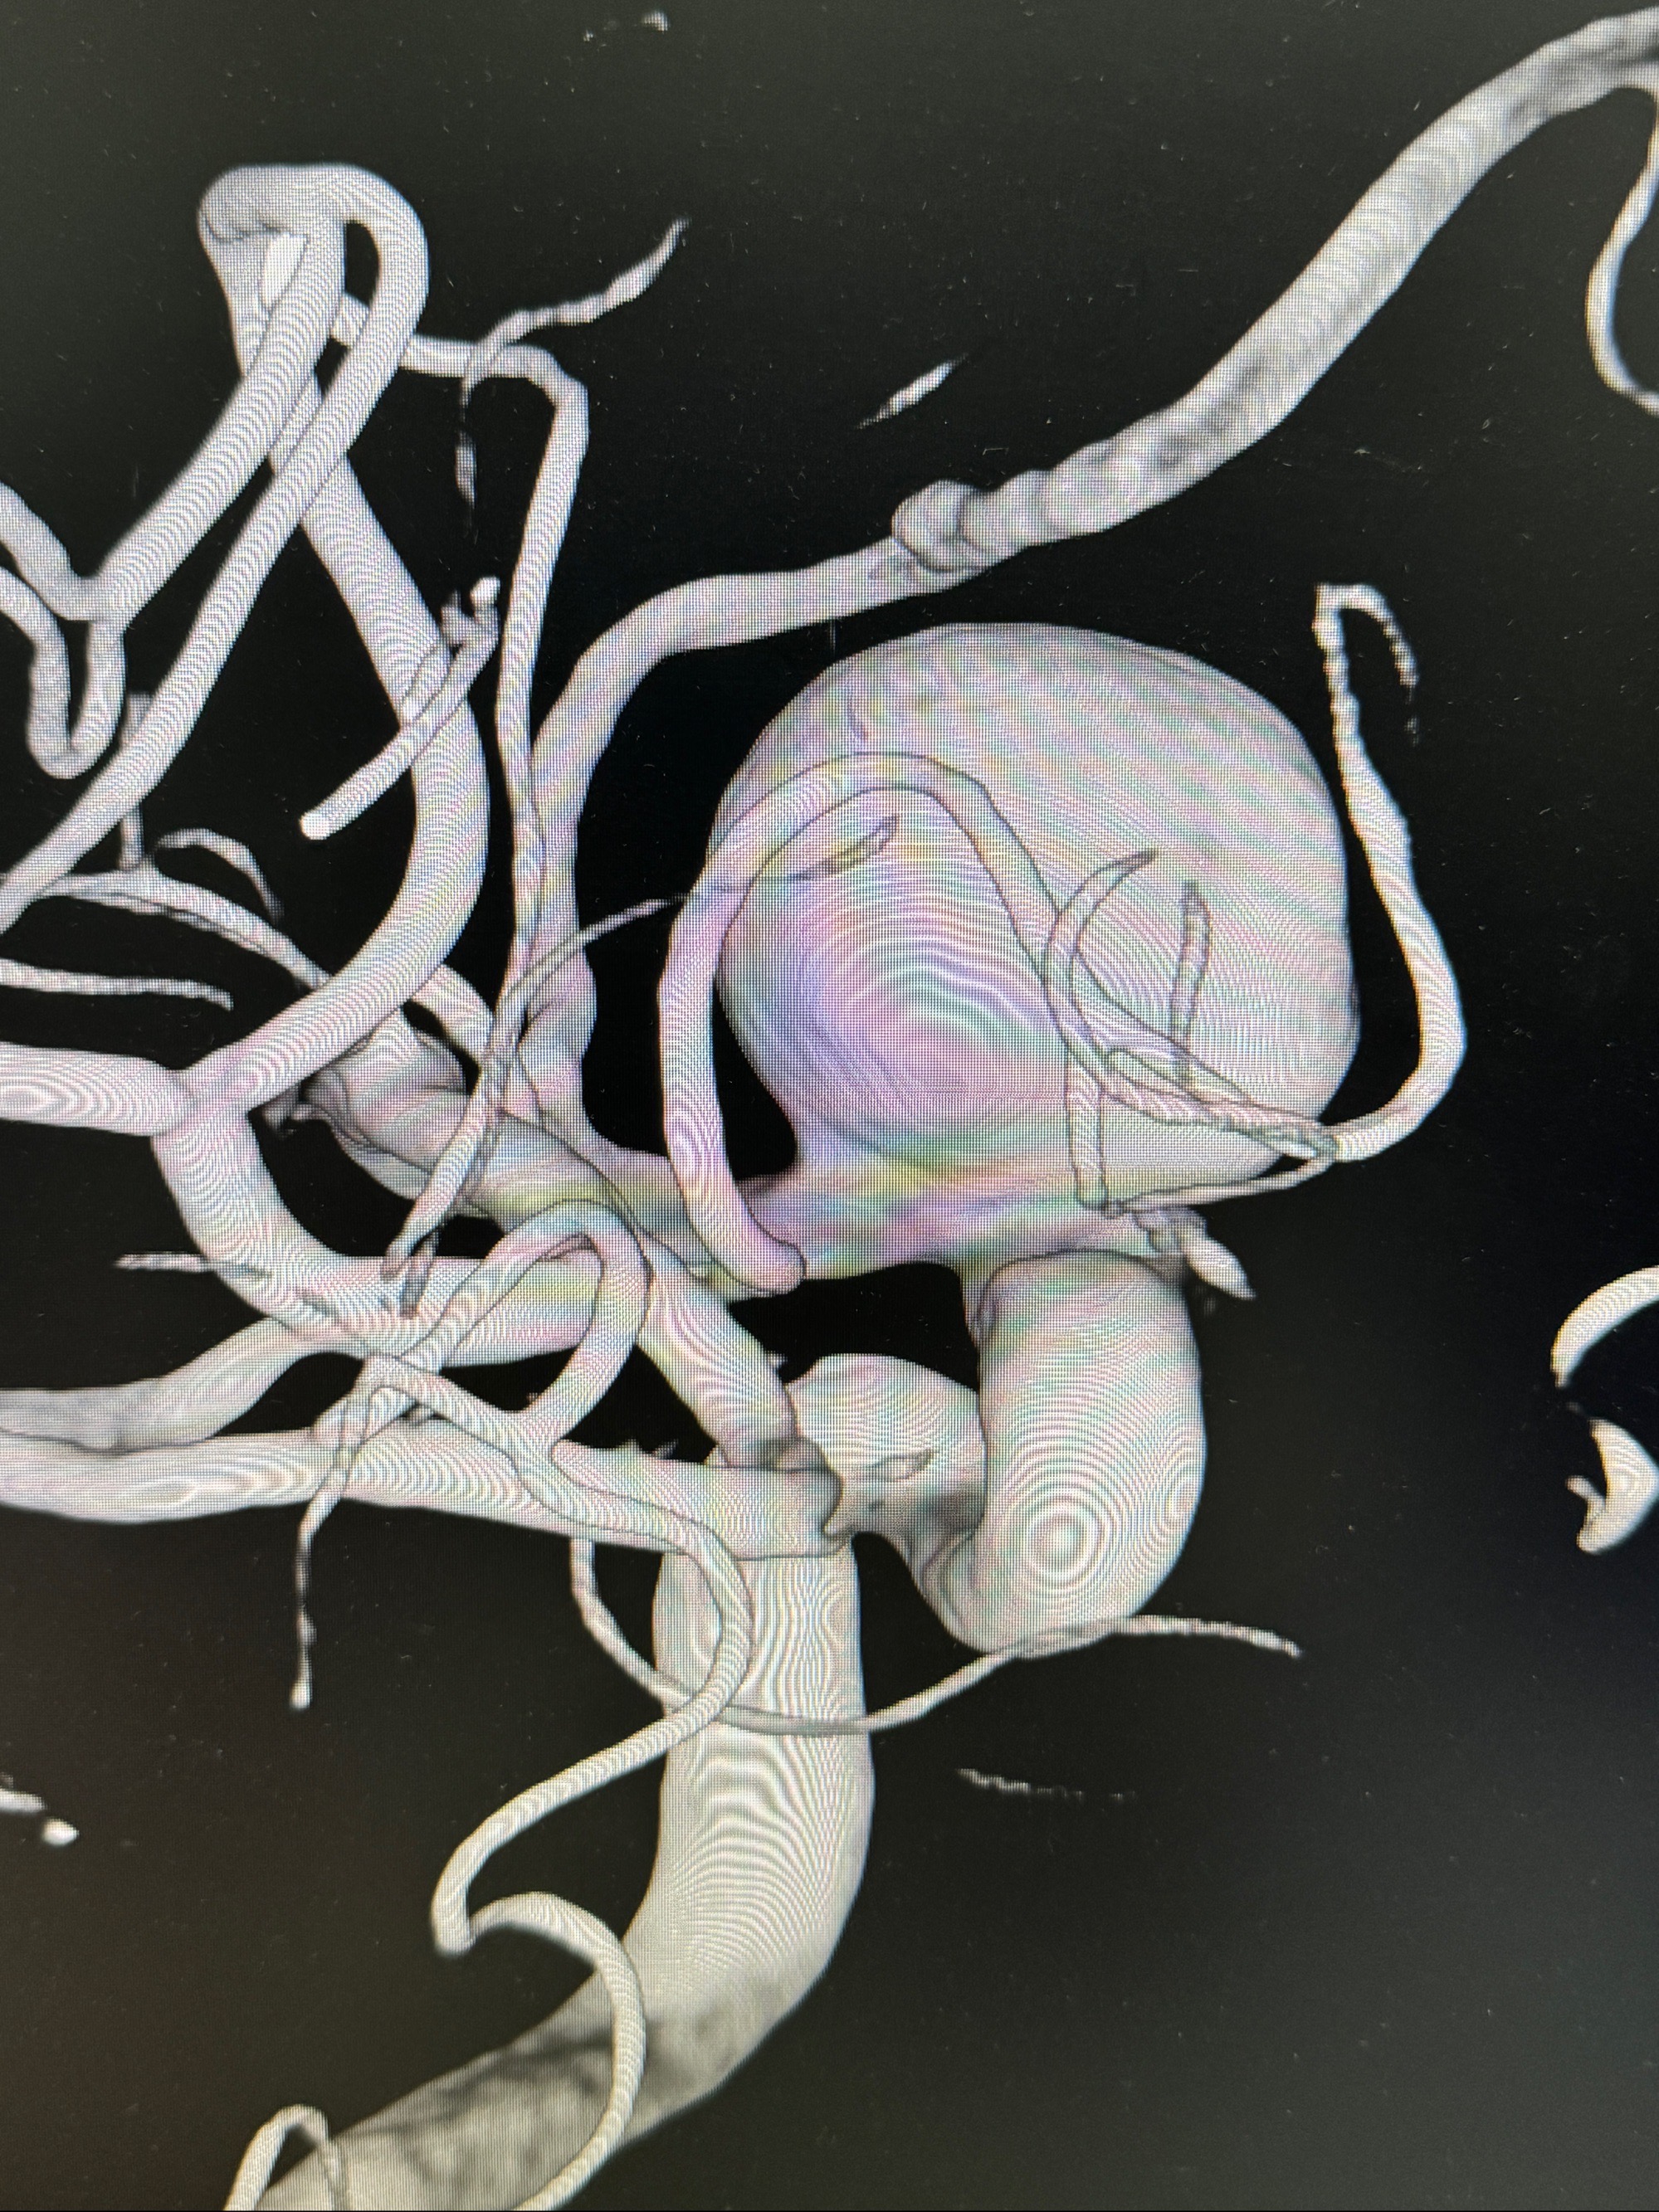

旋转3D展示动脉瘤局部的血管构筑

测量动脉瘤的大小:16*13.8*7.6mm大小,较原先变大,考虑双抗后瘤内血栓溶解可能

4.5-30mmTurbridge密网支架,于M1近心端打开

多角度显示支架打开情况